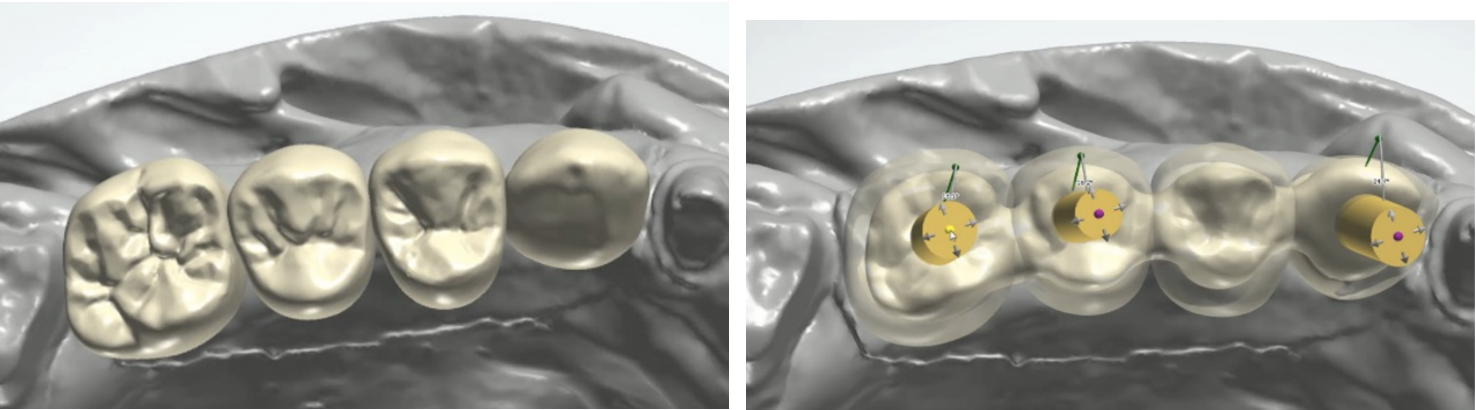

Once the data in STL format was acquired, the case moved to design development using CAD/CAM technology. ANGLEBase® seamlessly integrated into the workflow, ensuring a smooth transition from planning to manufacturing. The restoration was customised according to the patient's unique needs, thanks to the versatility of ANGLEBase®.

The abutment of choice to restore this patient was ANGLEBase®, since it offers flexibility, angular freedom and precision. ANGLEBase® allowed the prosthodontists to optimise the aesthetics and functionality of the restoration by precisely adjusting the screw access position and chimney angle. This resulted in a superior outcome for the patient.